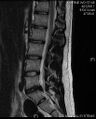

انزلاق غضروفي خلال تمزق في الحلقة (موضح بالتصوير بالرنين المغناطيسي).[9]

- التصوير بالرنين المغناطيسي هي الدراسة المعيارية الذهبية لتأكيد الاشتباه في انزلاق غضروفي. مع دقة تشخيصية تبلغ 97%، فهي الدراسة الأكثر حساسية لتصور الانزلاق الغضروفي بسبب قدرتها الكبيرة على تصور الأنسجة الرخوة. كما يتمتع التصوير بالرنين المغناطيسي بموثوقية أعلى بين المراقبين مقارنة بوسائل التصوير الأخرى. ويشير إلى انزلاق غضروفي عندما يظهر إشارة متزايدة مرجحة بـ T2 عند المنطقة الخلفية التي تغطي 10% من القرص. وقد أظهرت أمراض الانزلاق الغضروفي ارتباطًا بتغيرات النوع 1 من مقياس موديك. عند تقييم اعتلالات الجذور العصبية القطنية بعد الجراحة، فإن التوصية هي إجراء التصوير بالرنين المغناطيسي مع التباين ما لم يكن هناك موانع أخرى. يعد التصوير بالرنين المغناطيسي أكثر فعالية من التصوير المقطعي المحوسب في التمييز بين الأسباب الالتهابية أو الخبيثة للانزلاق الغضروفي. يُشار إليه في وقت مبكر نسبيًا في مسار التقييم (<8 أسابيع) عندما يظهر المريض مؤشرات نسبية مثل الألم الشديد والعجز الحركي العصبي ومتلازمة ذيل الفرس. التصوير الموتر الانتشاري هو نوع من تسلسل التصوير بالرنين المغناطيسي المستخدم للكشف عن التغيرات الدقيقة في جذر العصب. قد يكون مفيدًا في فهم التغييرات التي تحدث بعد أن يضغط القرص القطني المنفتق على جذر العصب، وقد يساعد في التمييز بين المرضى الذين يحتاجون إلى تدخل جراحي. في المرضى الذين لديهم شكوك عالية في اعتلال الجذور العصبية بسبب الانزلاق الغضروفي القطني، ومع ذلك فإن التصوير بالرنين المغناطيسي غامض أو سلبي، يوصى بدراسات التوصيل العصبي.[44] توفر الصور المرجحة الناتجة عن التصوير بالرنين المغناطيسي (T2) تصور واضح لمادة القرص البارز في القناة الشوكية.